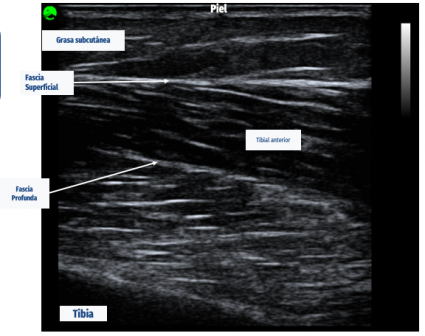

Constanza Rivas señala que, en base a dicha evidencia, los tejidos del sistema musculoesquelético en personas que poseen trastornos musculoesqueléticos no han sido estudiados. En ese sentido, decidió apuntar al tejido muscular para su investigación, siendo uno de los tejidos que posee mayores funciones de movimiento, además de ser un predictor de salud y de mortalidad, por lo que observó la calidad muscular y evaluar de manera funcional y morfológica los tejidos de una muestra de 101 profesores.